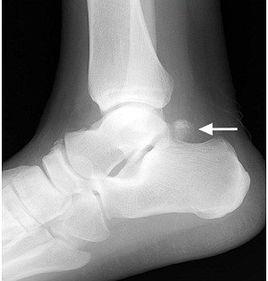

診斷:典型的缺損局部臨床表現,許多結合X 線平片、CT 掃描,即可明確問題診斷。

其他輔助檢查這種:線平片正側位及其他擅長不同方位平片即可顯示顱骨缺損的部位、範圍。掃描同X 線片相結合,不僅可以進一步明確顱骨缺損的部位與範圍,而且可以了解周邊顱骨及腦內、腦膨出組織情況,有利於手術。